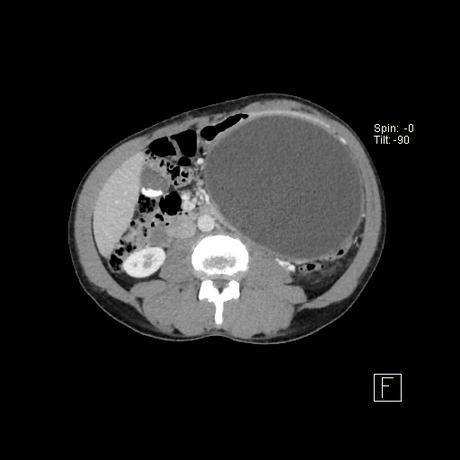

producen por la alteración de la estructura del conducto pancreático con la consiguiente pérdida y acumulación de jugo pancreático que da lugar a una necrosis grasa hemorrágica. No están revestidos por epitelio (por lo tanto, “pseudoquistes”), sino que una reacción inflamatoria grave da como resultado la encapsulación del quiste por tejido de granulación fibrosado. Esto suele tardar de 4 a 6 semanas 8,9 . En aproximadamente el 50% de los casos, el quiste conserva una comunicación con el conducto pancreático 2 . Estos quistes son más problemáticos de tratar y es más probable que reaparezcan.